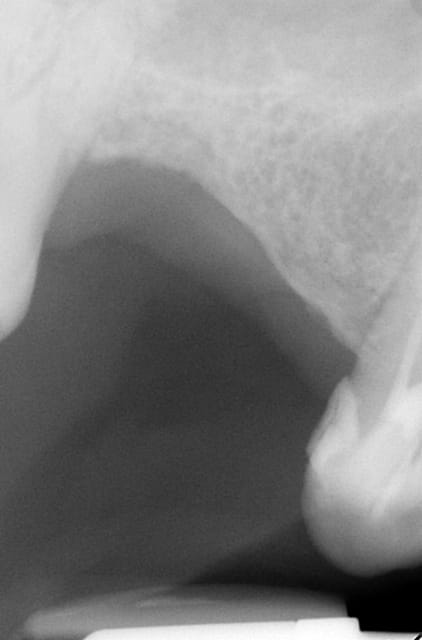

En ce qui concerne la précision, dans ce cas là et pour eviter une augmentation, j ai du placer l implant en mesio palatinal ( voir radio initiale)

En mesurant la hauteur de l os dans le septum ( dans le DVT), celui était seulement de 3 mm. Voilà pourquoi l´implant n est pas dans le septum. L´os a été condensé,la stabilité primaire a donc pu atteindre 50 Ncm.